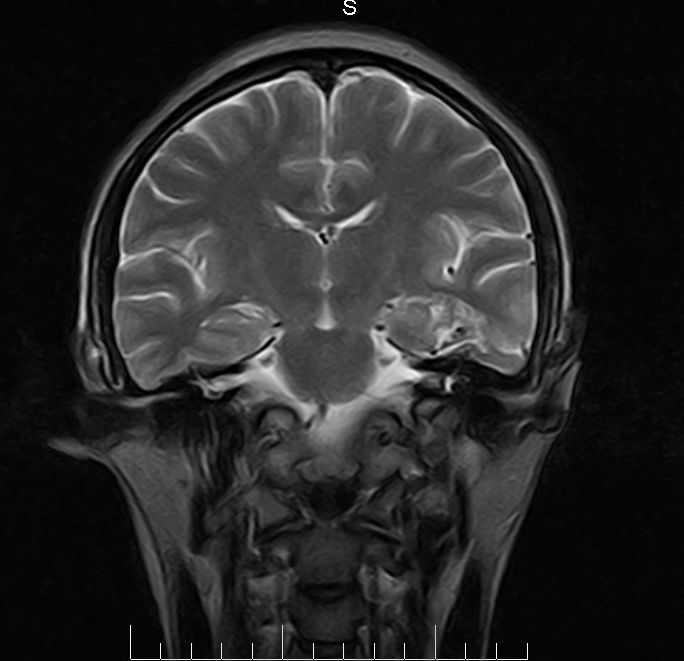

标题: MRI2379:30岁,男,癫痫10年,请各位看一下;CT示:左颞叶钙 [打印本页]

标题: MRI2379:30岁,男,癫痫10年,请各位看一下;CT示:左颞叶钙

左颞叶区见不规则点状混杂信号影

考虑血管畸形

支持2楼 左颞叶区见不规则点状混杂信号影,考虑动静脉畸形。

考虑左侧颞叶脑血管畸形(avm)。

考虑左侧颞叶脑血管畸形(avm)。----t1低等高混杂信号,t2等高信号周边较多流空血管影[冠状位明显],mra左侧大脑中动脉受压,远侧聚集.